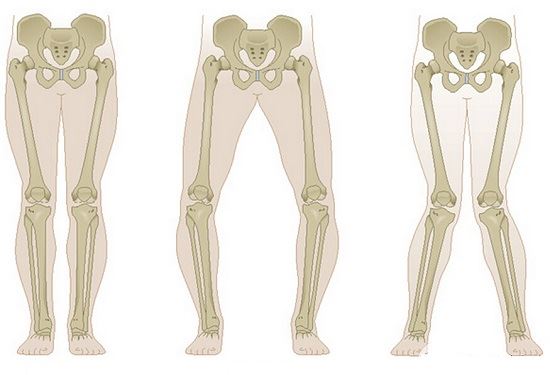

膝关节是一个复杂的机械结构,肌肉长度和力线的改变会引发额外的磨损并导致畸形,关节对缝不正会使局部压力骤增,软组织的紧张和挛缩会让关节软骨加速磨损……这类问题引发的疼痛往往都是酸痛、隐痛,疼痛的位置相对浅表,用手指仔细按压能够找到明确的痛点,疼痛在运动(例如:跑步后)后会有所加重,运动停止后疼痛又很快会减轻。